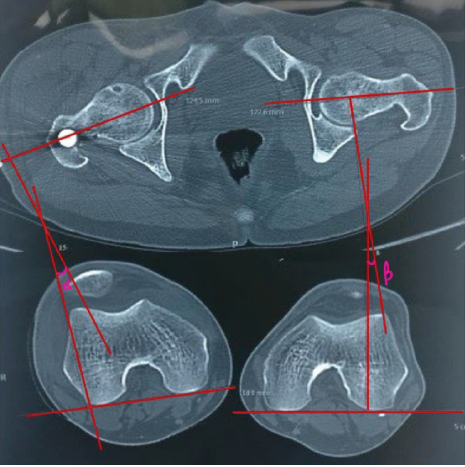

This prospective observational study was conducted at a tertiary-level trauma center in Delhi over 18 months after obtaining approval from the respective institutional ethics committee. Written informed consent was obtained from all participants before inclusion. Thirty skeletally mature patients (aged ≥18 years) presenting with closed diaphyseal or diaphyseo-metaphyseal femoral fractures who were managed with closed antegrade IMN were enrolled consecutively. Patients with pathological fractures, compound injuries, old neglected fractures, abnormal femoral anteversion in the contralateral limb, uncontrolled systemic comorbidities, or pregnancy were excluded from the study. All procedures were performed under spinal anesthesia with the patient positioned supine on a fracture table. A standard lateral approach was used to access the proximal femur. Closed reduction was achieved using traction and image intensifier guidance. Rotational alignment was approximated intraoperatively by evaluating the cortical diameter and lesser trochanter profile compared to the contralateral limb. Post-operative assessment of femoral torsion was performed using CT. The rotational alignment was measured using the Jeanmart method [6], which calculates the angle between a line drawn along the posterior condylar axis distally and a line through the femoral neck axis proximally (Fig. 1).

Figure 1: Computed tomography (CT)-based measurement of femoral malrotation using the Jeanmart method. Axial CT slices at the femoral neck and condylar levels demonstrating angle α on the operated side and angle β on the contralateral side; the difference (α-β) represents the degree of femoral malrotation.